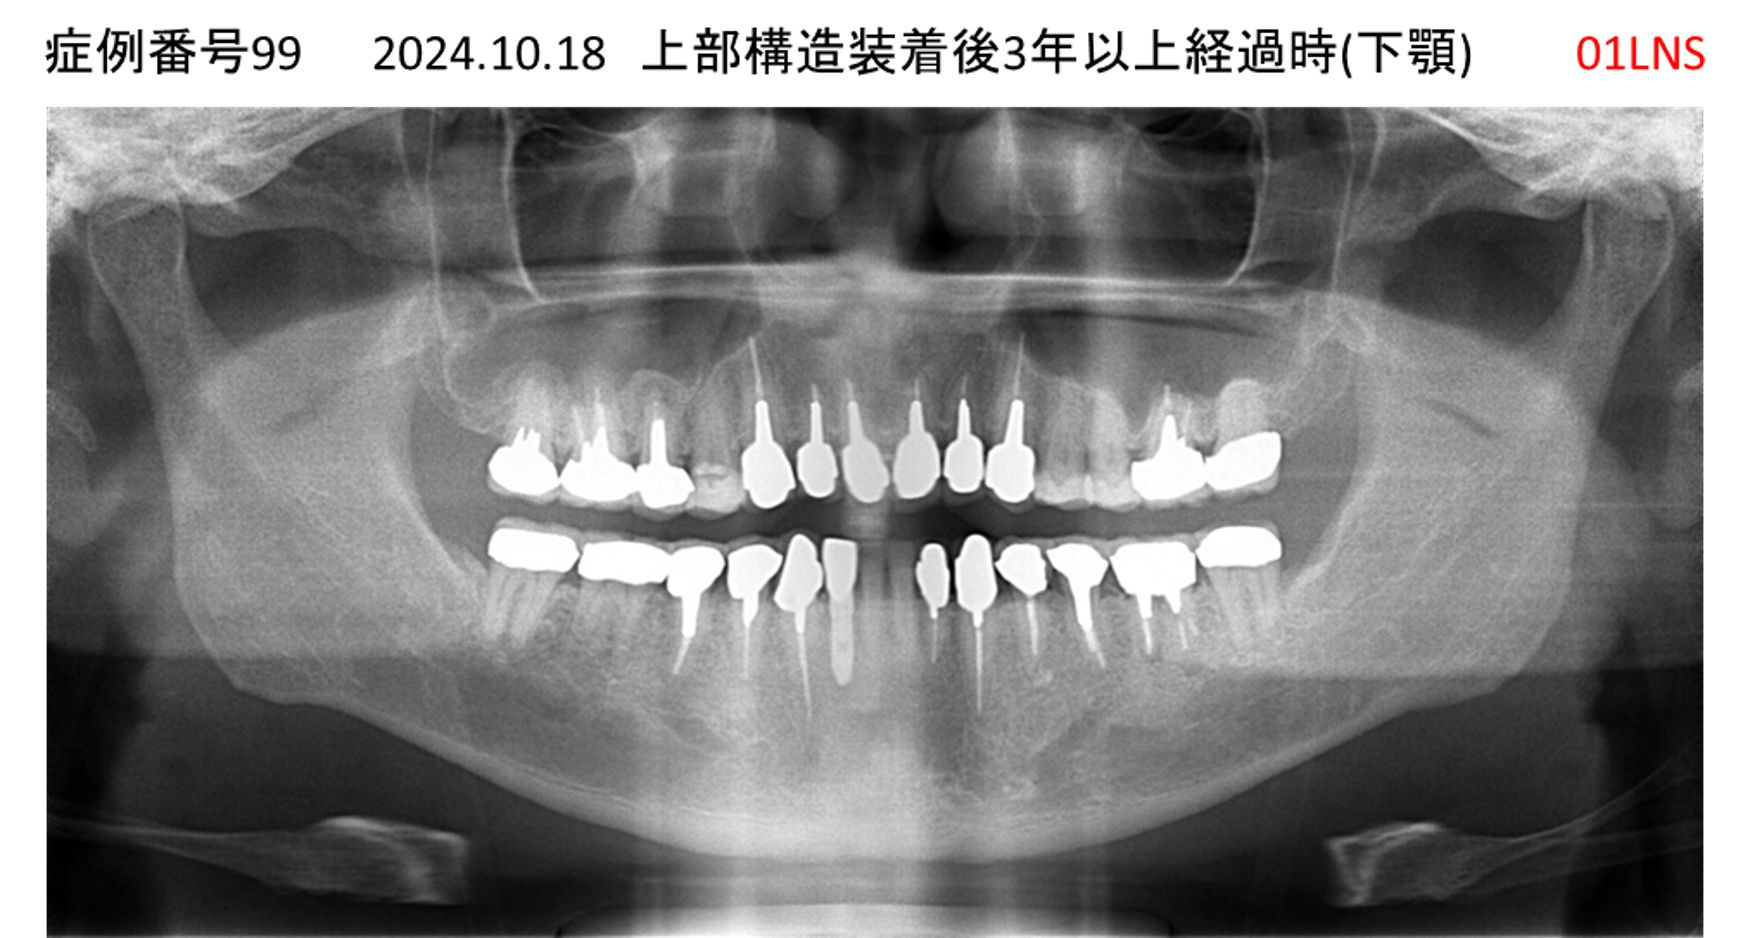

全く噛めない患者様のインプラント症例

| 治療名称 |

インプラントAGC |

| 治療費用 |

860万円+税 |

| 治療期間 |

12か月 |

| 患者さんの症状(主訴) |

全く噛めない、ごはんが後もに食べられるようになりたい、人前で口元を隠したくない |

| 治療内容 |

サイナスリフト、GBR、インプラント、AGC |

| 治療結果 |

しっかり噛めて踏ん張ることができる。食べ物をを選ばなくて済む、何でも食べられる、体重が増えた。見栄えがきれいすぎて自分じゃないみたい |

| 治療の注意点(リスク/副作用) |

インプラントが壊れたら再治療が必要 |